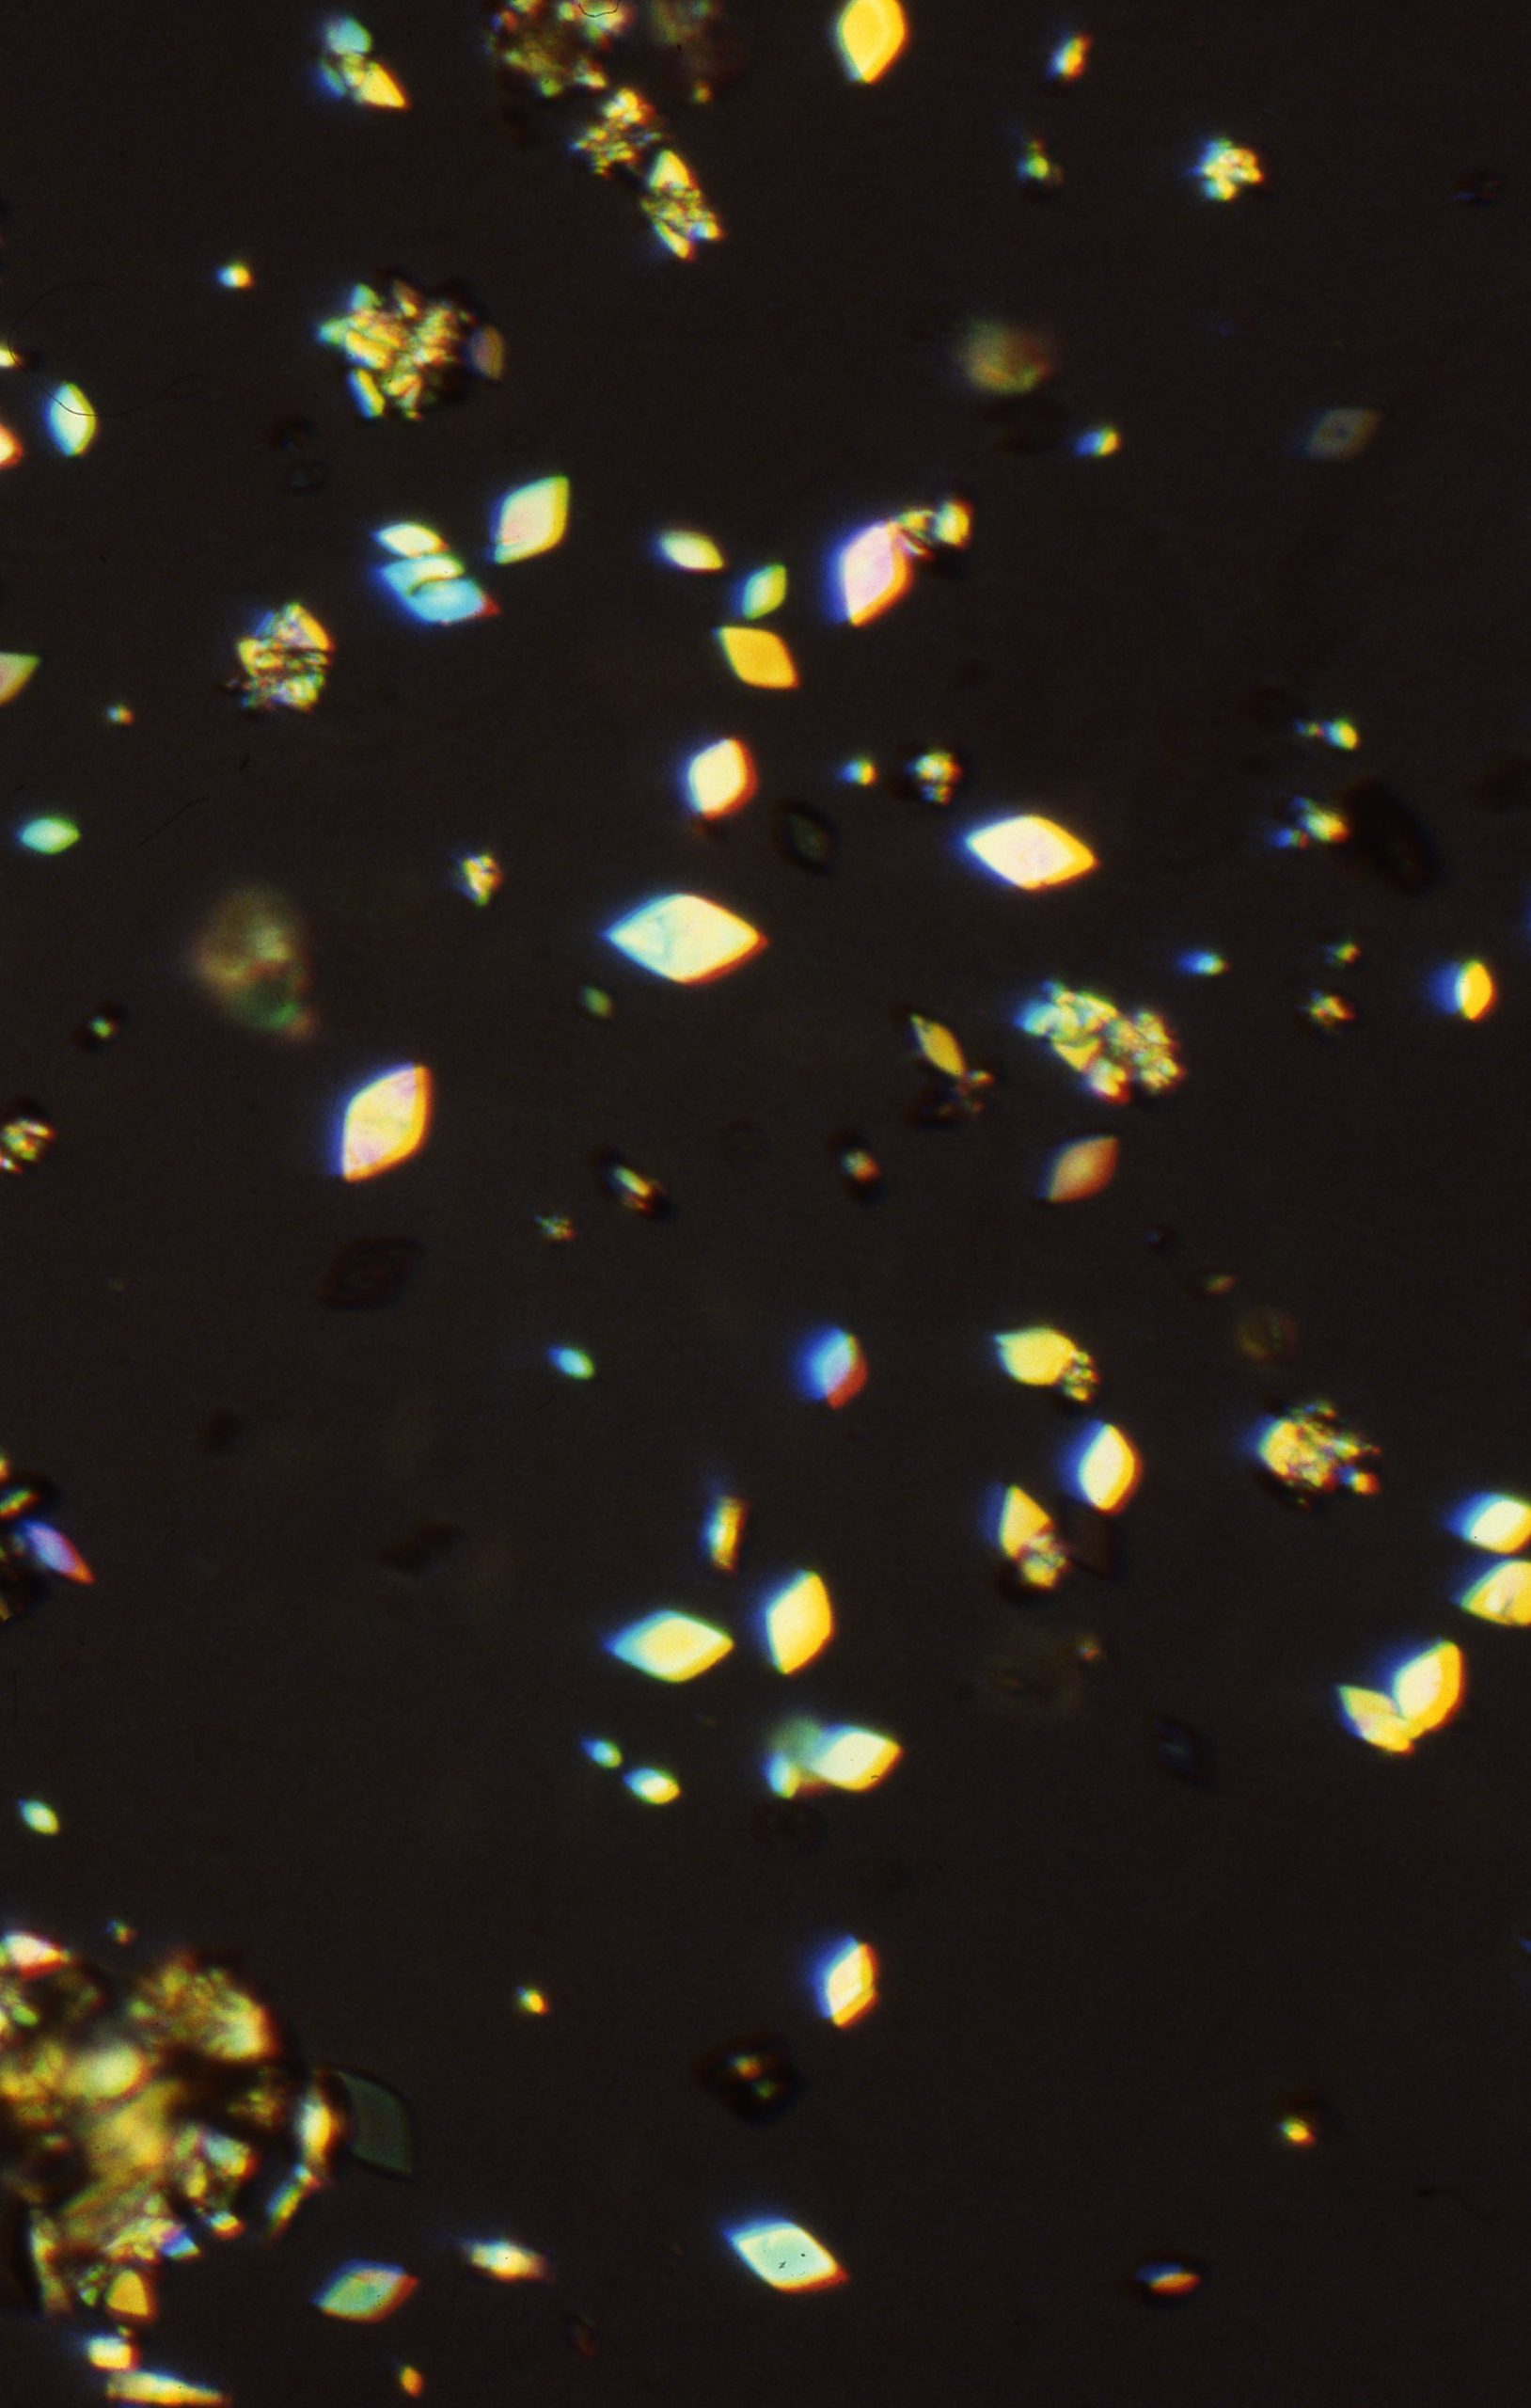

Uric acid crystals are found in acid urine, the crystal vary more in morphology than any other type of crystalThe morpholoy varies from needles, hexagonal, whestone forms, rosttes or rhombic plates Mag 10X Hexagonal forms Mag 10X Mag 10xX Mag 40X Mag 40X Mag 40X Mag 40x Mag 40X The above microphotographs are uric acid crystal with polarized light